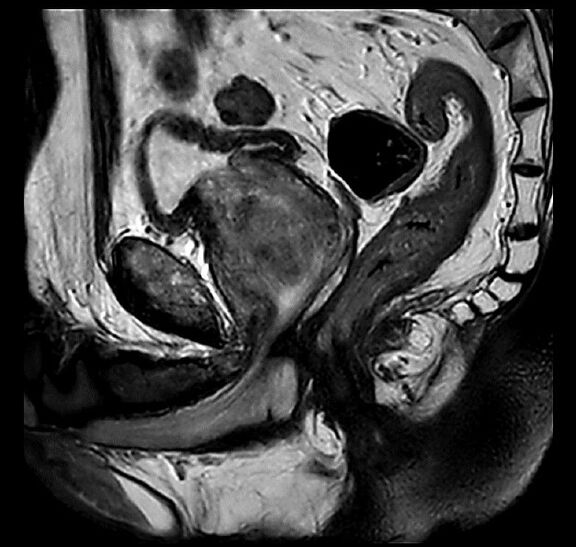

Beispiele von MRT-Prostata Aufnahmen